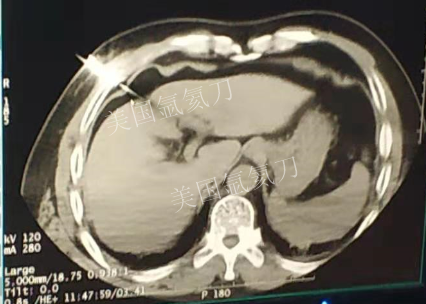

59岁男性肝部氩氦刀手术治疗